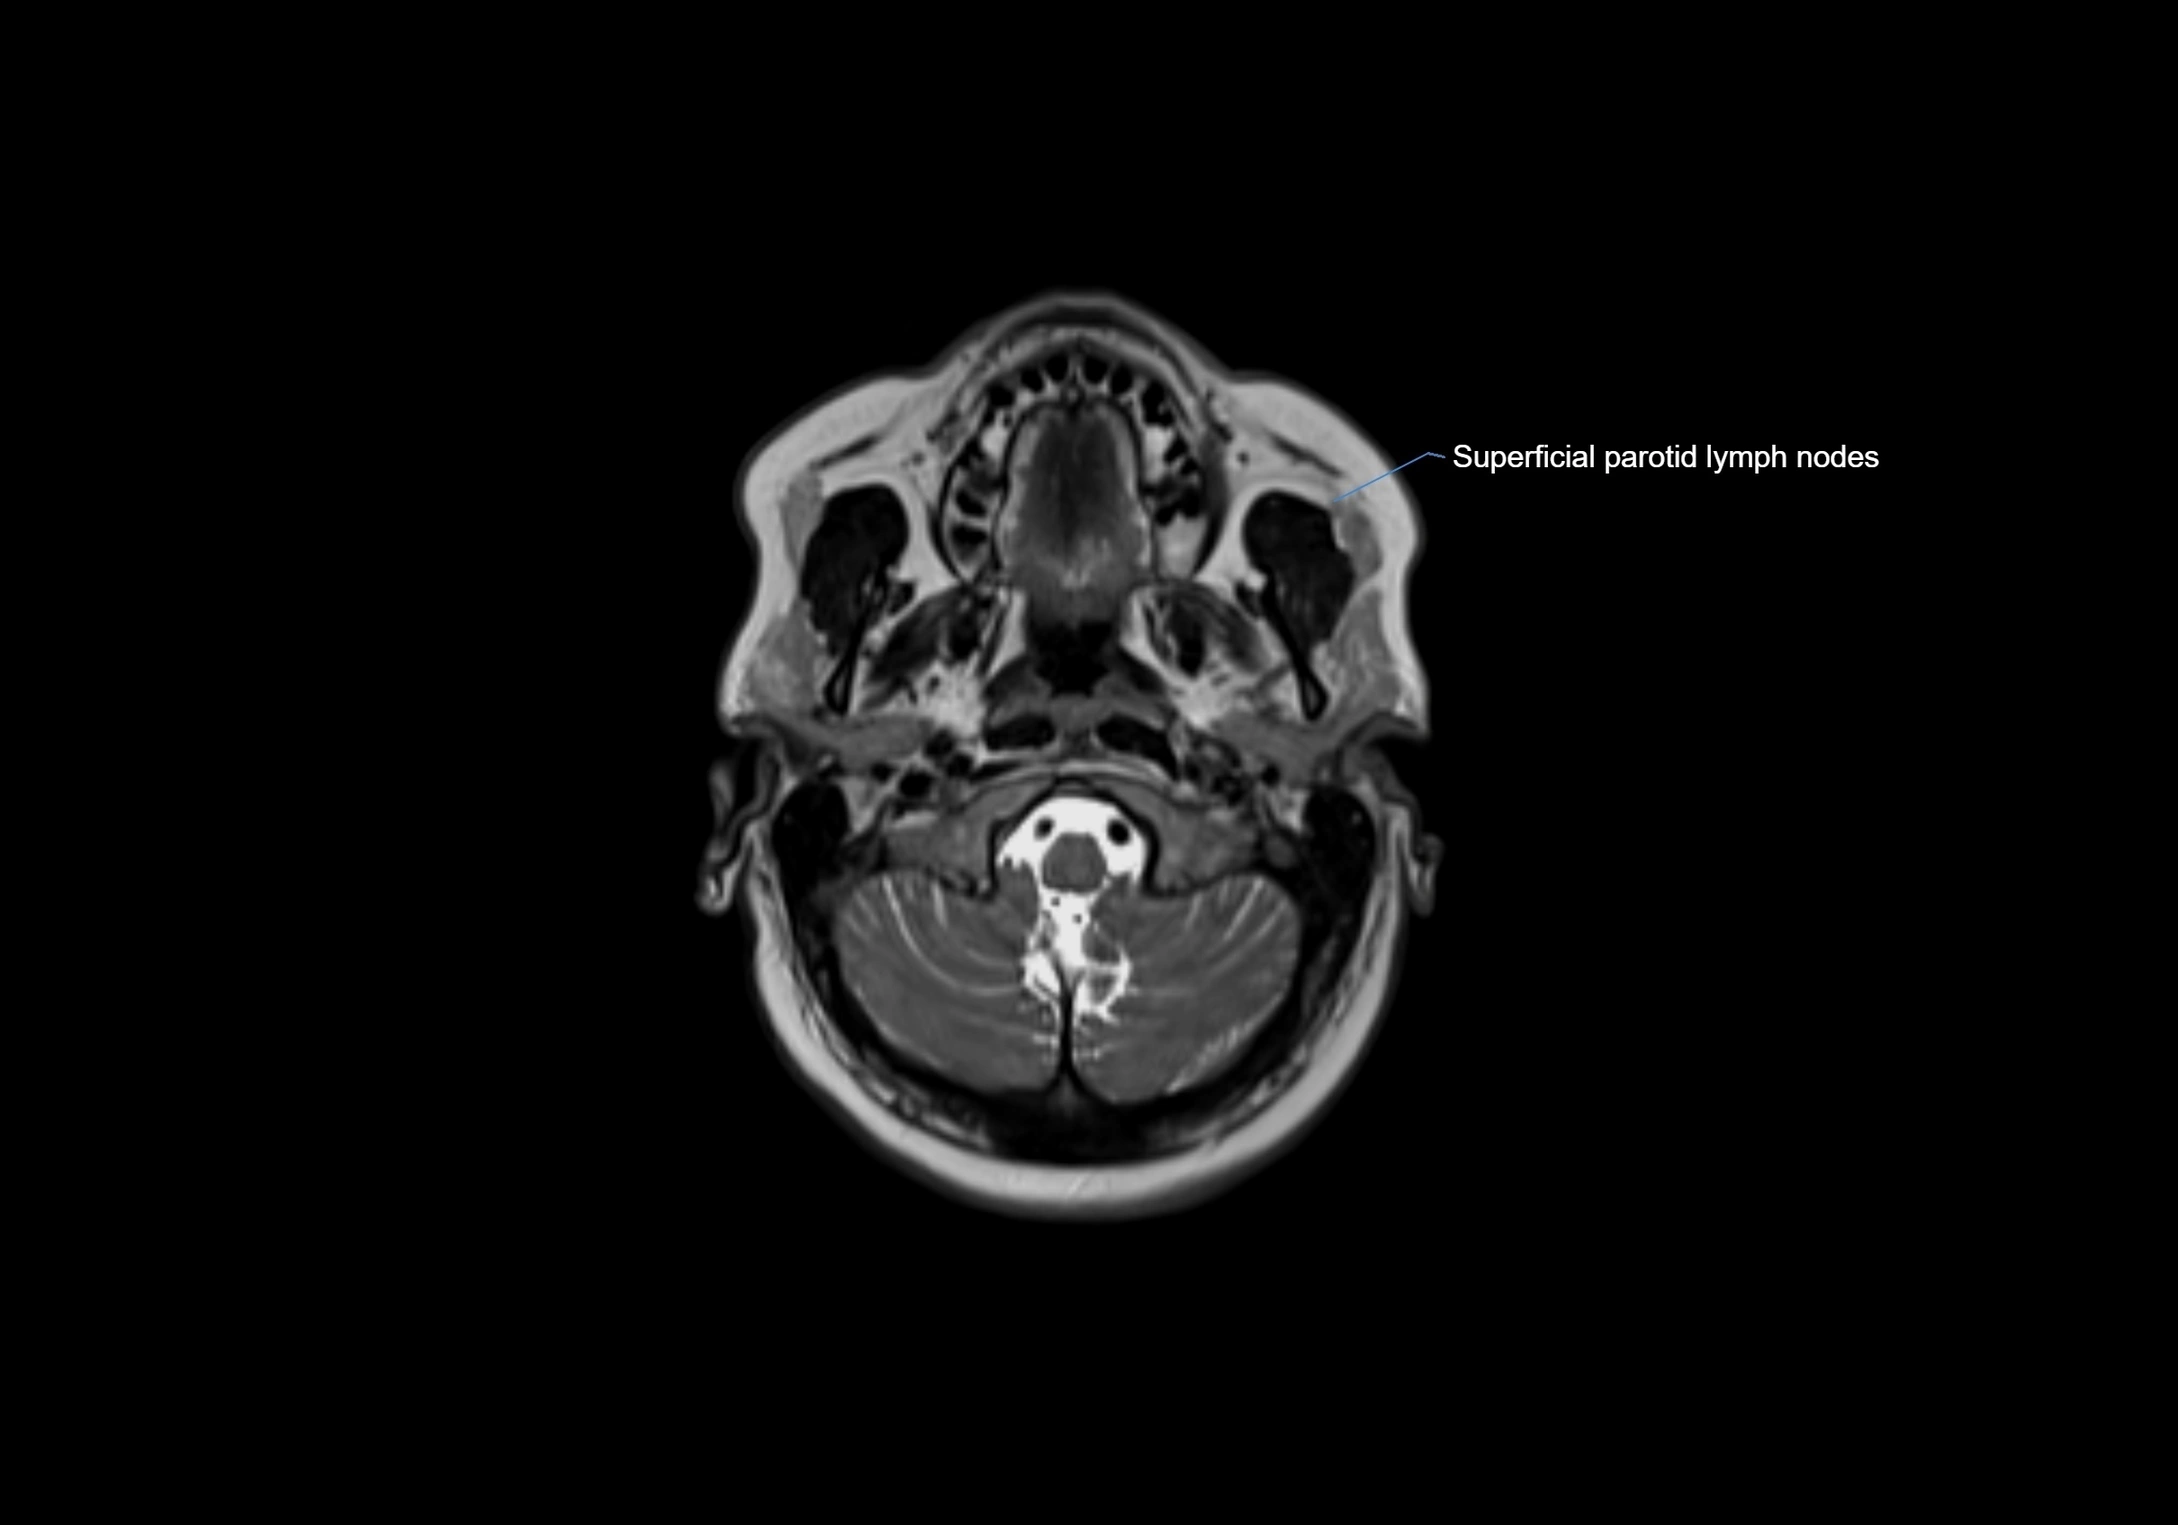

• Found along primary lymph node chains, including preauricular, submandibular, parotid, and occipital regions

MRI images

image